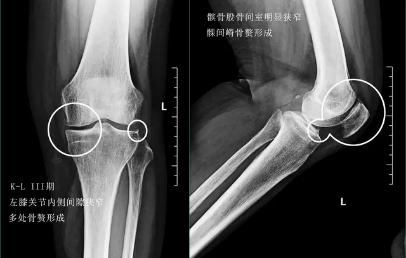

三期患者:3期的患者不仅有了骨赘大量形成,而且关节间隙已经开始发生了明显的狭窄,患者的症状会越来越严重,很多会表现出来蹲起的疼痛,甚至有的患者不能长时间的行走,否则次日关节就会有明显的肿胀,有的患者在屈伸关节的过程当中会听到响声,类似于冬天我们用脚踩雪的那种响声。

在此阶段我们通常仍然会采取关节内注射的办法以及一些保守治疗的办法,缓解患者的痛苦。患者也可以口服仙灵骨葆这一类的中成药。

四期患者:4期的骨关节炎患者关节已经出现了严重的畸形,这个时期患者会非常的痛苦,关节会有严重的畸形,通常不能行走很长的距离,有一些患者甚至行走500米就疼痛难忍了。而且患者通常会出现比较明显的休息痛以及静息痛,什么意思呢?就是说,不动也痛。

此时我们只有通过进行关节置换手术的办法,才能帮助患者来解决痛苦。医生也知道很多患者不想做全膝关节置换术,所以说现在也研究出来单髁的置换手术,也算是一种保膝治疗。